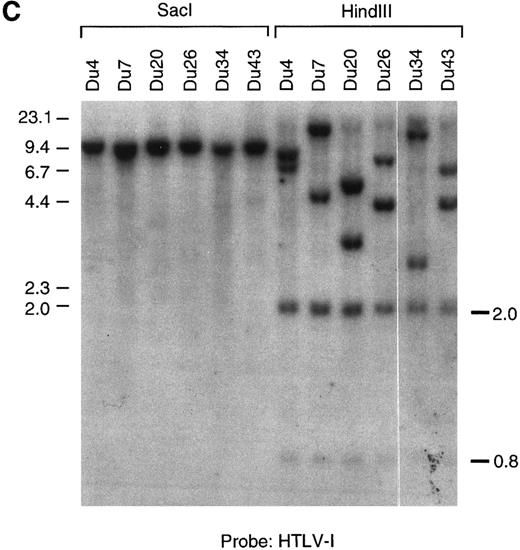

(A through C) Southern blot analysis of the HTLV-I provirus and T-cell receptor gene rearrangement in human T-cell clones. Genomic DNA digested with EcoRI (A, B) Sac I, or HindIII (C) was hybridized with the probe indicated. All clones except Du35 were infected with HTLV-I. (D) Restriction map of the HTLV-I genome. Numbers indicate the predicted length in kb of restriction fragments.

(A through C) Southern blot analysis of the HTLV-I provirus and T-cell receptor gene rearrangement in human T-cell clones. Genomic DNA digested with EcoRI (A, B) Sac I, or HindIII (C) was hybridized with the probe indicated. All clones except Du35 were infected with HTLV-I. (D) Restriction map of the HTLV-I genome. Numbers indicate the predicted length in kb of restriction fragments.

Infected T cells in blood are polyclonal and contain a single provirus.Genetic analysis has shown that fresh leukemic cells from ATL patients generally contain a single provirus, which may be incomplete,49,50 whereas HTLV-I–transformed cell lines cultured in vitro often contain multiple integrated proviruses51 (and references therein). T-cell cloning technology provides an opportunity to examine provirus copy number, integrity, and expression at the single-cell level in primary, nonimmortalized T cells. Southern blot analysis using an HTLV-I probe showed that most infected clones contain one integrated provirus. This was shown by the presence of a single hybridizing fragment when DNA was digested with EcoRI (which does not cut within the provirus) and also by the presence of two chromosomal junction fragments using HindIII (Fig 1). Two notable exceptions to this rule are the clones Ph1C and Mu16. Ph1C is a CD8 clone containing three discrete proviruses.52 Mu16 DNA gave a smear on EcoRI digestion. The EcoRI smear in Mu16 was not due to partial digestion or sample degradation as reprobing of the filter with a T-cell receptor gene probe gave two discrete bands (Fig 1B). These data are most consistent with the presence of multiple HTLV-I integration sites in the Mu16 clone, a hypothesis confirmed by genetic analysis of single-cell subclones (unpublished data, May 1992). Analysis of T-cell receptor gene rearrangement showed that all clones, including Ph1C and Mu16, were of single cell origin. No two clones so far tested from a single individual contained the same provirus integration site or T-cell receptor gene rearrangement, supporting previous reports that infected cells in the peripheral blood are largely polyclonal in origin (Fig 1B).44,53,54 This observation is easily reconciled with a report documenting the existence of clonally expanded virus-containing cells in the blood of carriers, as each expanded clone is thought to represent no more than 1% of the total T-cell population.15